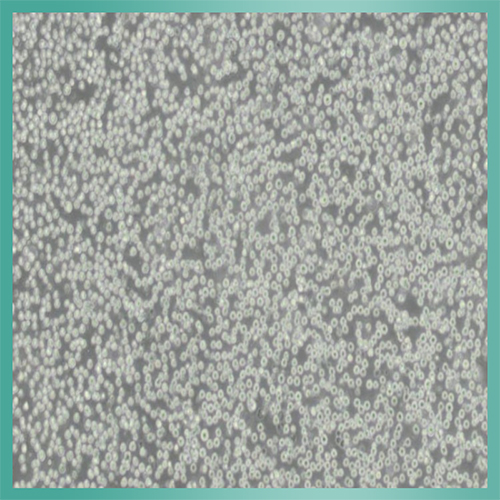

AtT-20细胞_小鼠垂体瘤细胞背景描述 : ATT-20_细胞生长时不贴壁,而结成细胞团悬浮生长。研究表明,ATT-20_细胞能抗脊髓灰质炎病毒。

细胞形态:圆形(成串)

注意事项:该细胞为悬浮聚团生长,生长速度较慢。